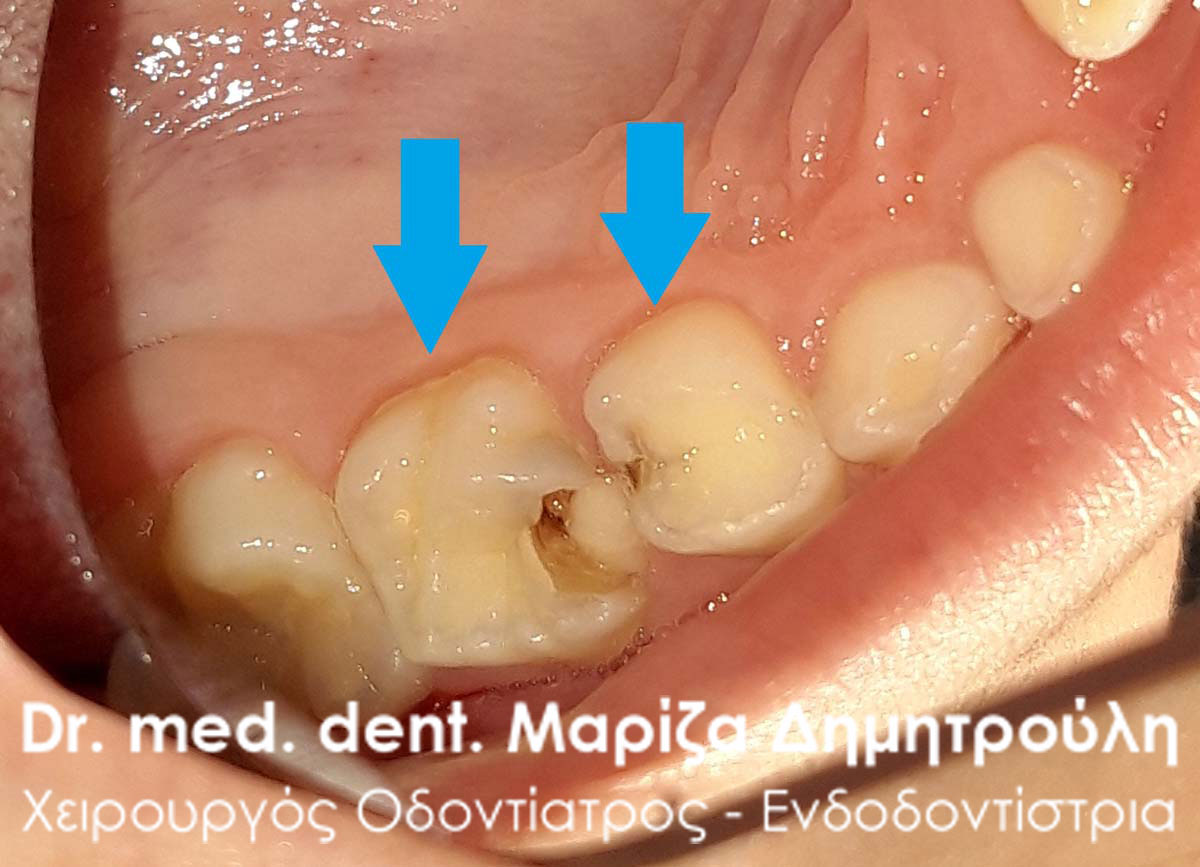

Ο νεαρός πονούσε πάρα πολύ όταν έτρωγε καθώς είχε δύο σχετικά μεγάλες τερηδονικές αλλοιώσεις στους 2 νεογιλούς γομφίους της άνω γνάθου. Τα δόντια αποκαταστάθηκαν με 2 σφραγίσματα ρητίνης στην ίδια συνεδρία.

ΠΡΙΝ

ΜΕΤΑ